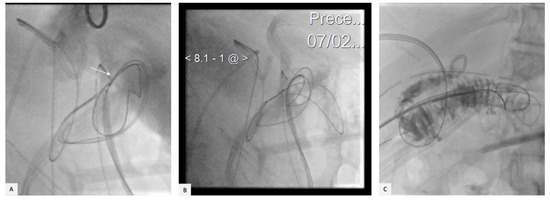

2. Case Presentation